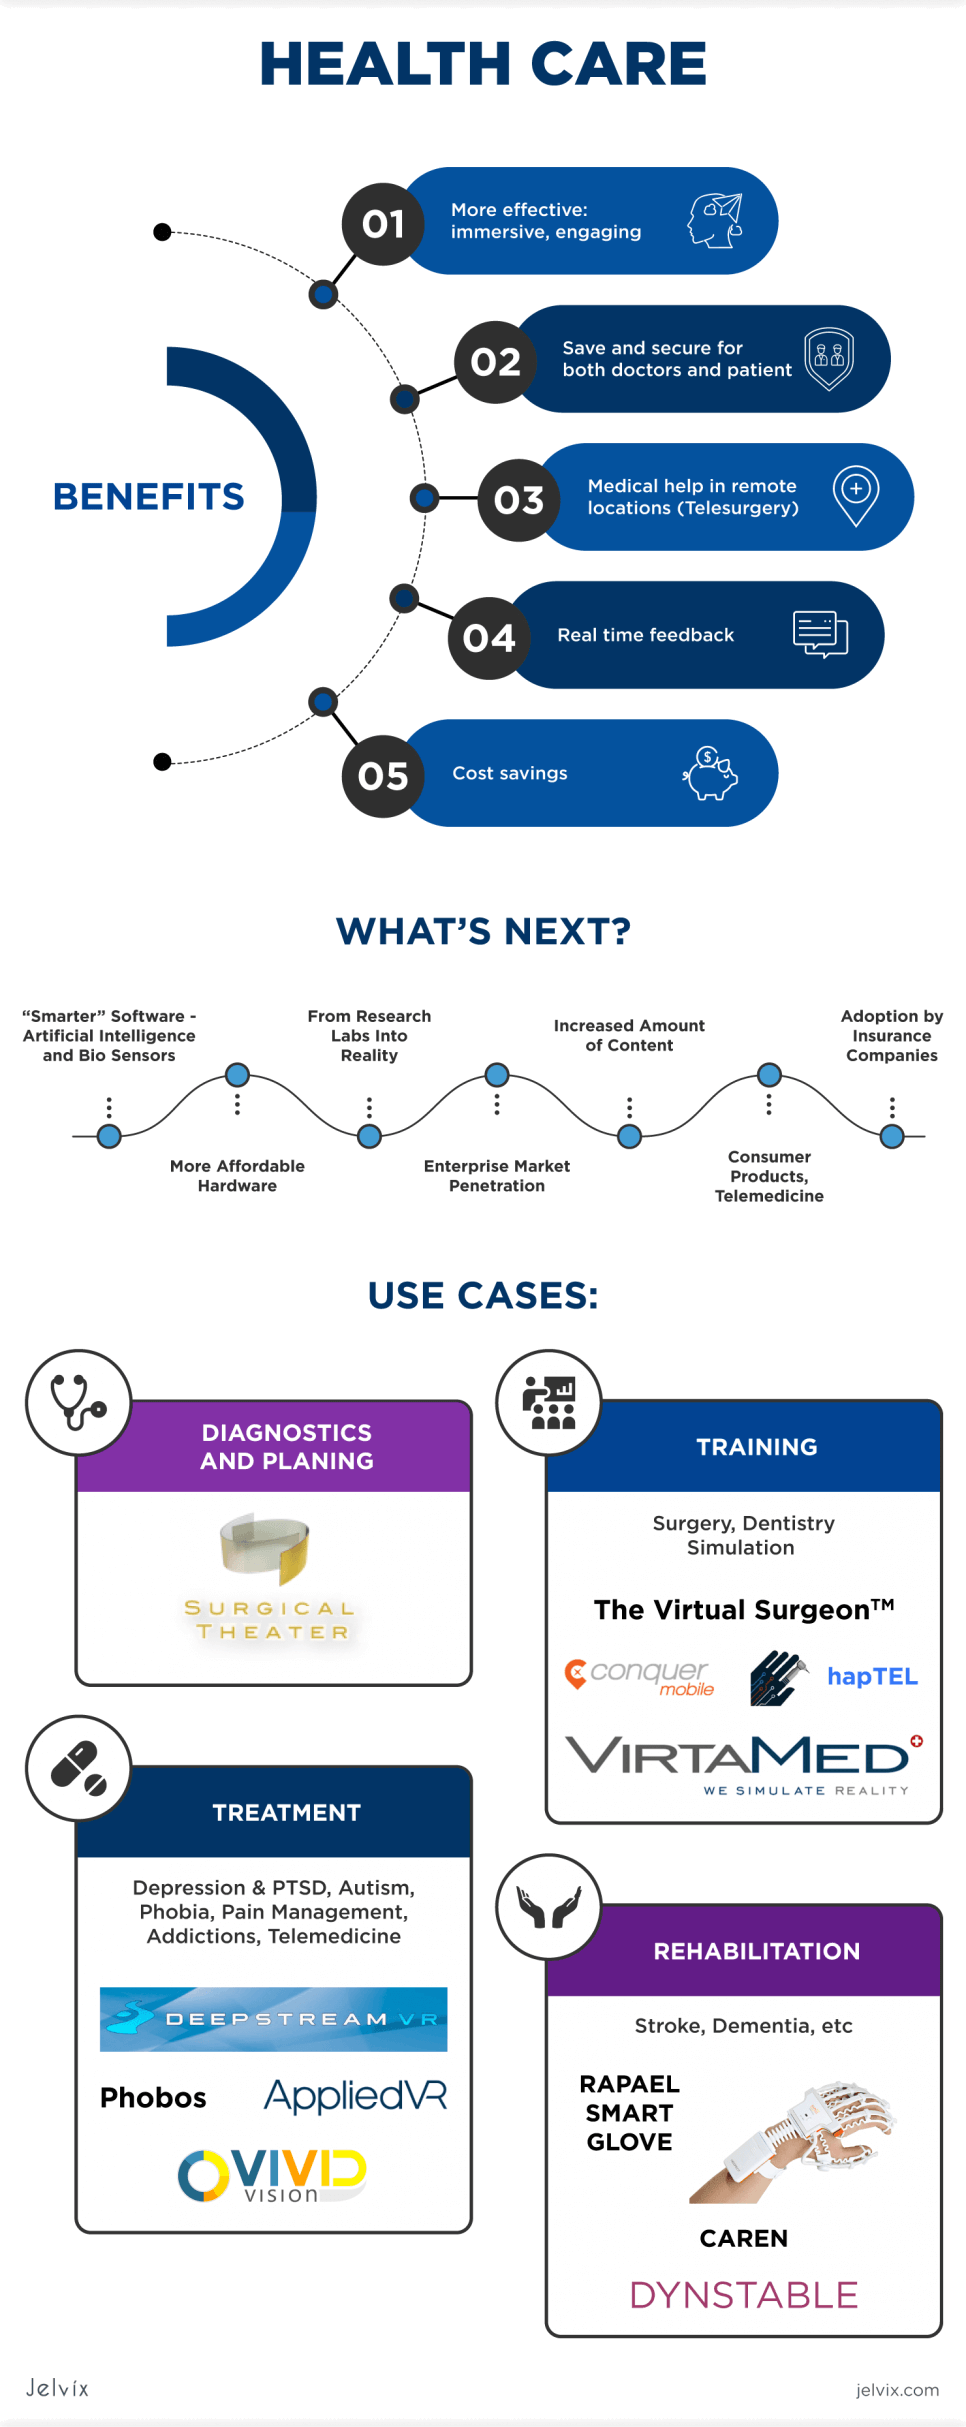

ARTICLE - Virtual Reality in Healthcare

By Vitaliy Ilyukha, Head of Technology | Jelvix | Acessed on April, 2022

Today virtual reality in healthcare is on a rapid rise, and many well-known companies are using it in a novel way to improve the health care system all around the world. The healthcare industry used virtual reality throughout its various sectors to provide high-quality care to patients and medical professionals alike. On top of that, virtual reality is being used in everything from surgical preparation to patient illness and therapy.

Infographic - Virtual Reality in Healthcare

By Vitaliy Ilyukha, Head of Technology| Jelvix | Accessed on April, 222

Full article by Vitaliy Ilyukha | Jelvix | Accessed on April, 2022

By Vitaliy Ilyukha, Head of Technology| Jelvix | Accessed on April, 222

Full article by Vitaliy Ilyukha | Jelvix | Accessed on April, 2022